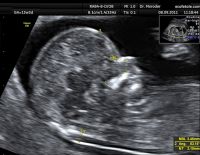

Đo độ mờ da gáy là gì và ý nghĩa khi thực hiện trong thai kỳ

Một trong những kiểm tra cần thiết trong thai kỳ mẹ cần thực hiện là đo độ mờ da gáy. Việc đánh giá thai nhi có nguy cơ bị bệnh Down hay không chính là nhờ vào phương pháp này. Tuy nhiên, tính chính xác...